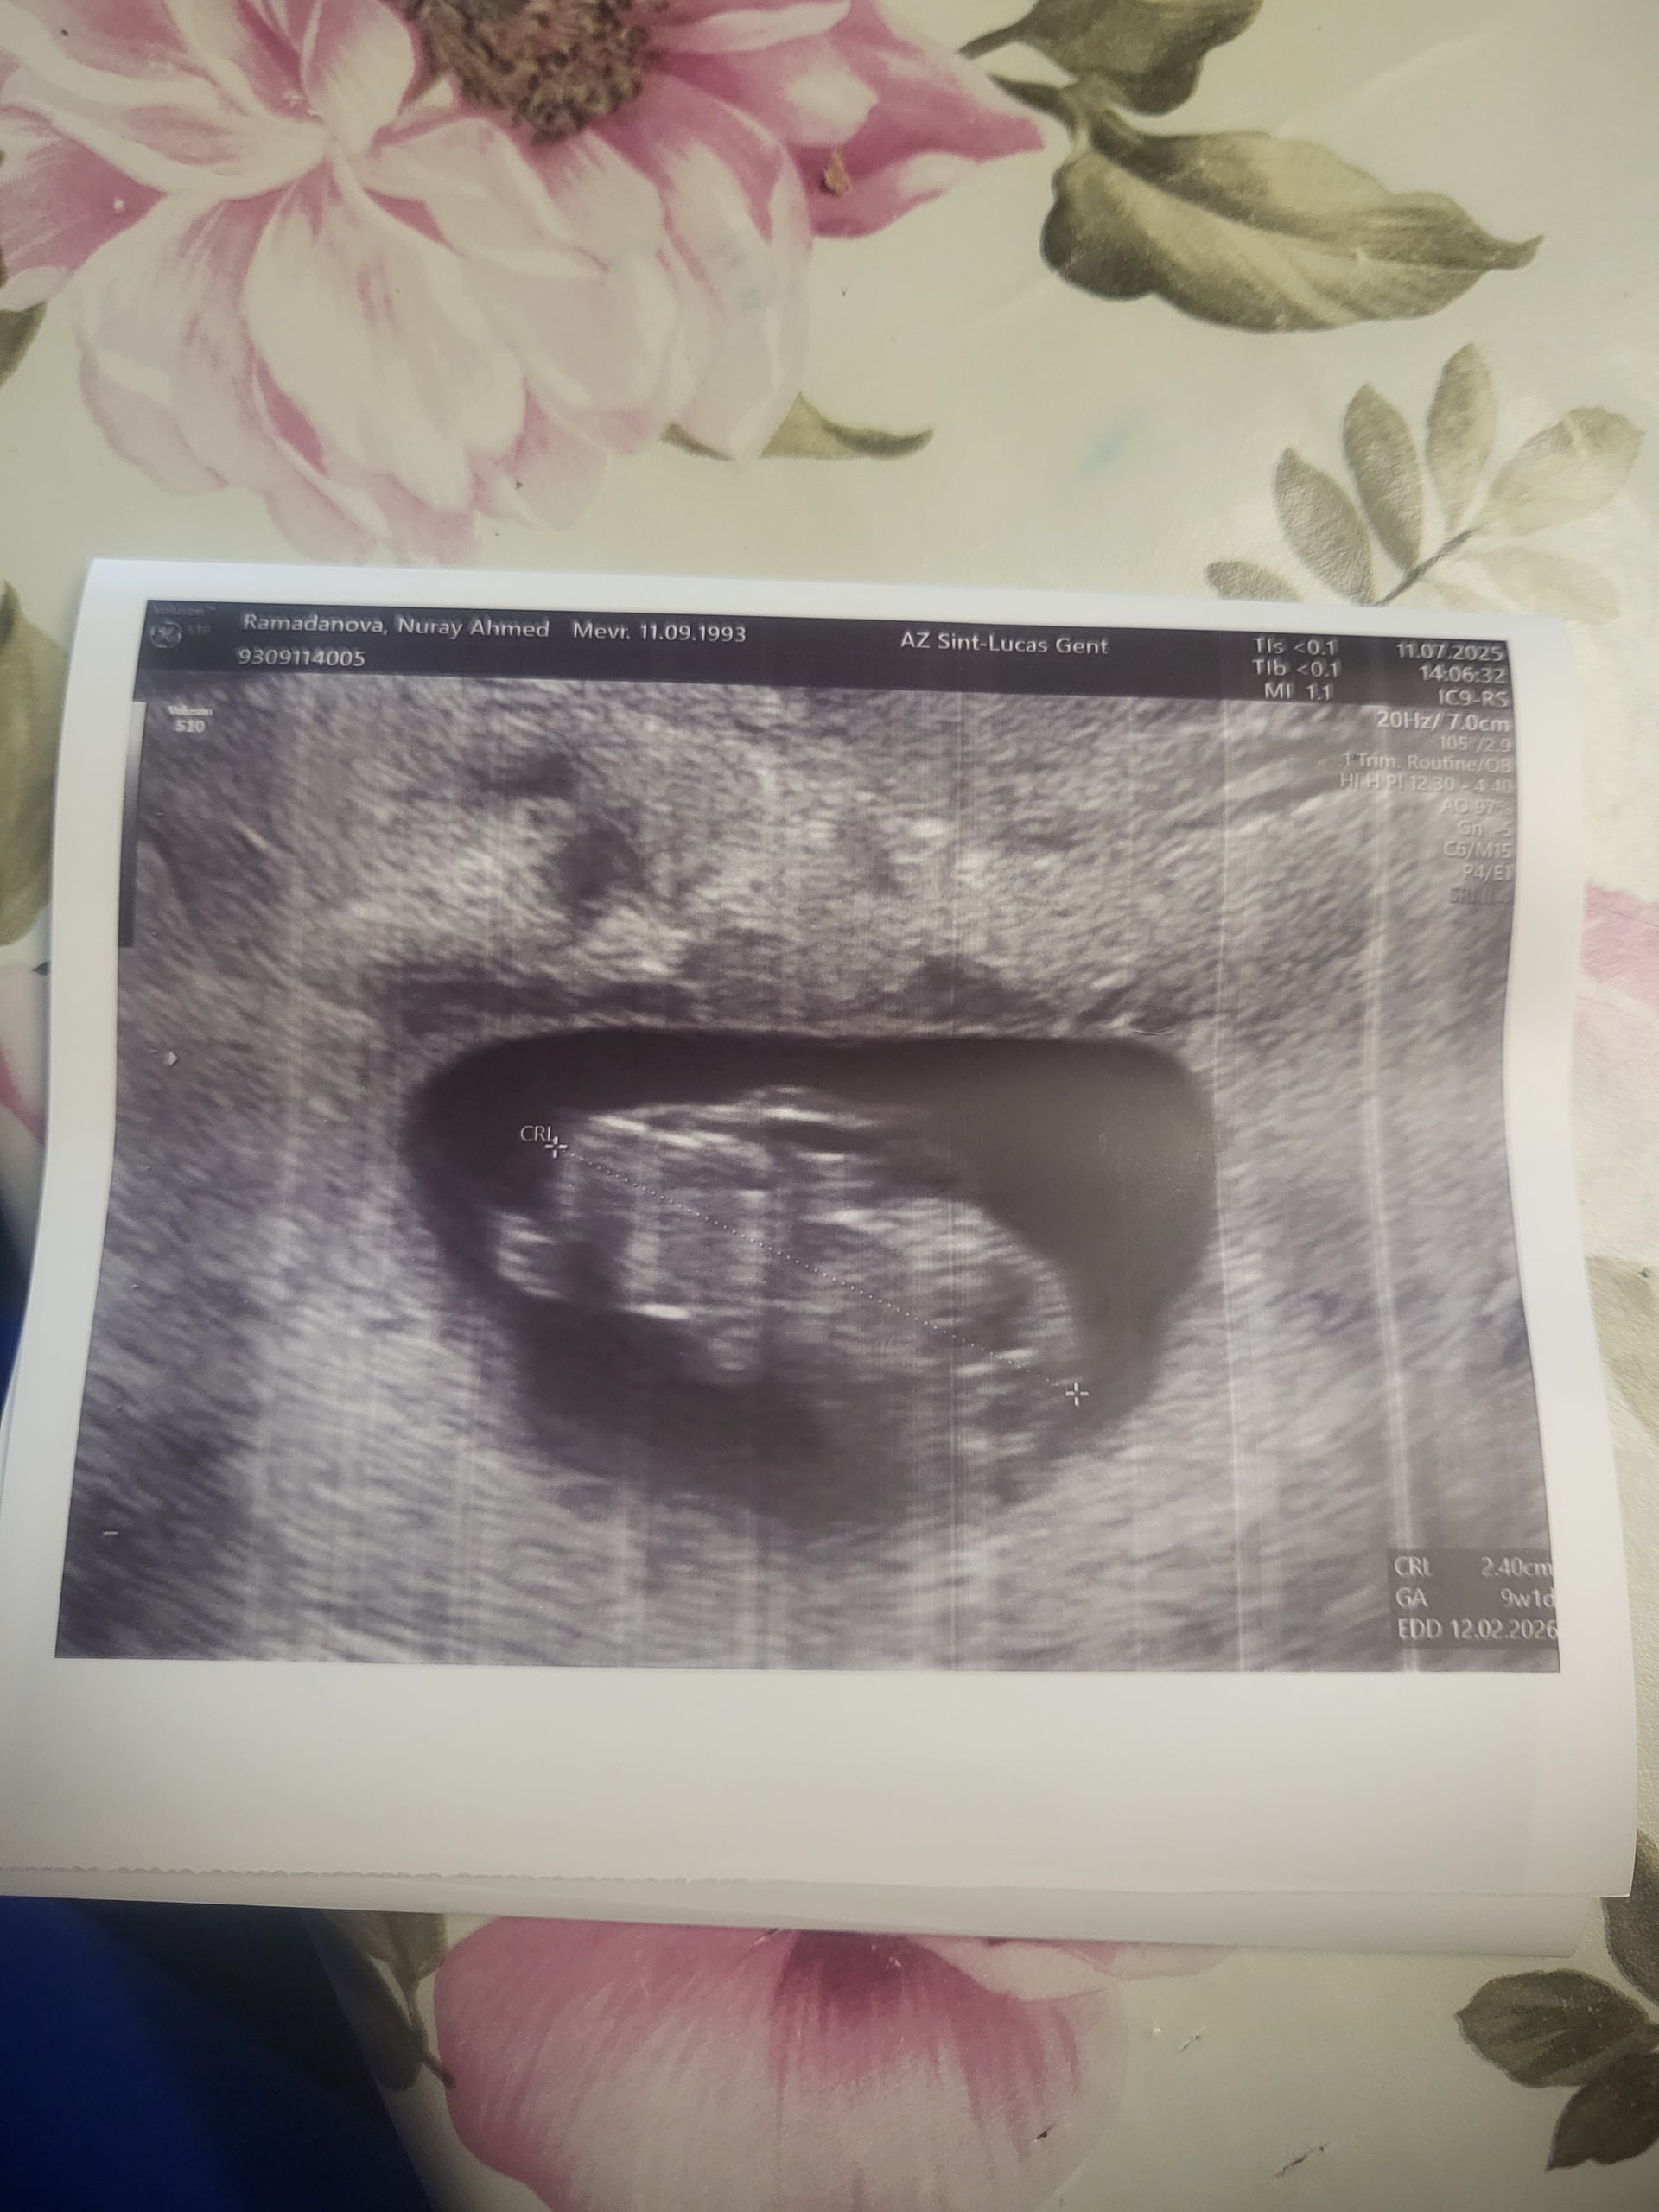

Banada cinsiyet tahmini yaparmisin

Kız bebiş kesesi gibi ![]()

Erkek bebiş kesesi gibi

Canım devletler yanlış cinsiyet söylüyorlar bazen bunun için özele gitsem kesin bı bilgi alabilirmiyim sence yarın 2 tarama yapılacak 3 ve 4 cu taramaya gerek olurmu acaba

Erkek bebiş kesesi gibi ![]()

Kuzum ben özele gittiğim halde başka bir özelde 13+3 de öğrendim cinsiyetini bebeğimin bence makinenin kalitesine bağlı bı de Dr tabi işinin ehli olmalı